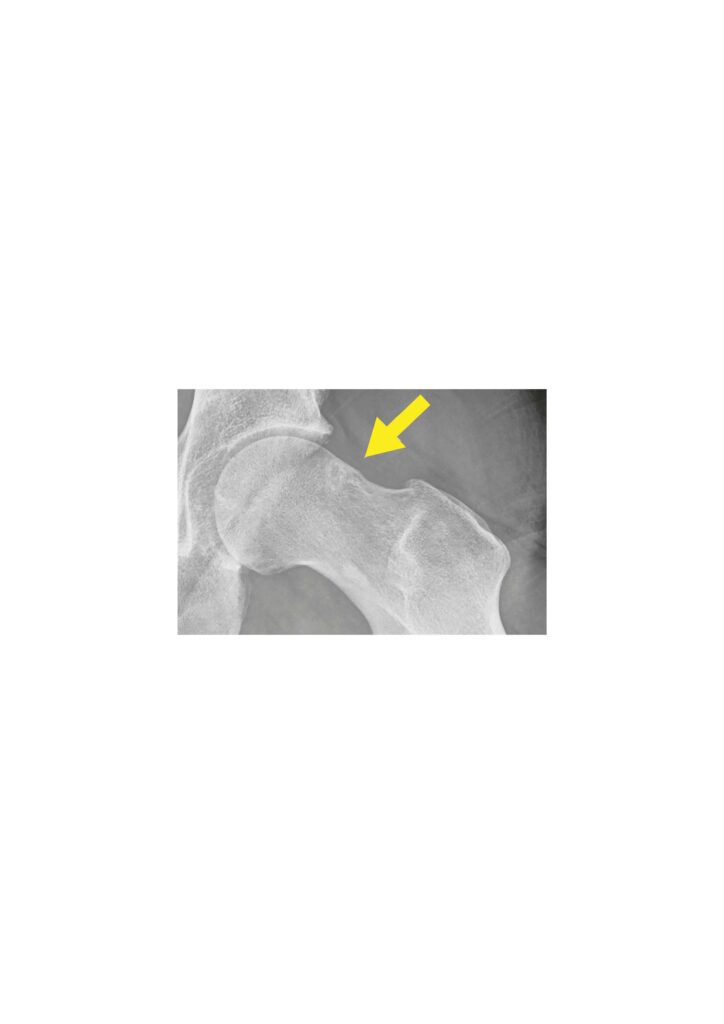

Hüftarthroskopie (Gelenkspiegelung):

- Minimalinvasive Technik mit kleinen Hautschnitten

- Behandlung von Labrumrissen

- Korrektur des femoroazetabulären Impingements (FAI)

Minimal-invasive, offene Operationen:

- Umformung bei Wulstbildung am Kopf-Hals-Übergang bei CAM-Impingement